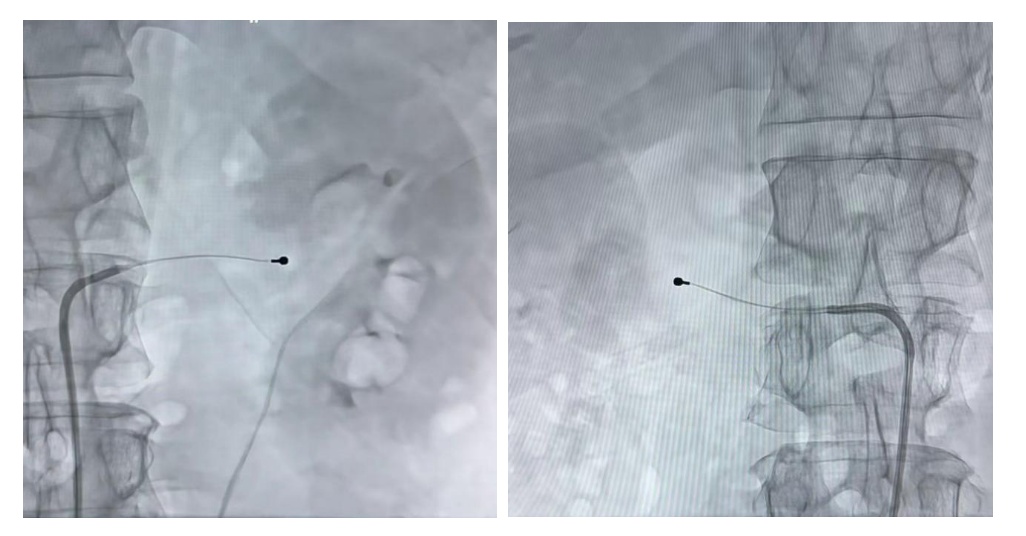

导管在左右肾动脉影像图

“传统消融是‘盲目扫射’,而我们采用的msRDN技术实现了‘精准打击’,只针对过度兴奋的交感神经,不损伤血管壁,提升了手术安全性与疗效稳定性。”徐亚伟教授介绍。

作为典型的微创介入手术,RDN全程无需开刀,仅需局部麻醉,通过大腿根部股动脉穿刺置入消融导管,1小时左右即可完成手术,患者当天就能下地活动,具有创伤小、恢复快的显著优势。临床数据表明,多药联合治疗仍不达标的高血压患者接受RDN手术后,收缩压平均可下降10-20mmHg,部分患者能减少药物用量甚至停药,降压效果可稳定维持3-10年以上。